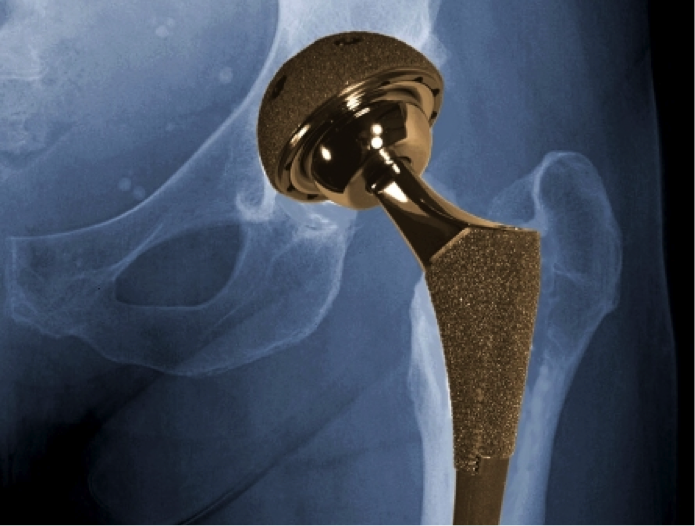

Metal-on-metal hip implants – either used as ‘cap’ for the femoral bone in a hip resurfacing procedure or as a full implant in total hip replacement surgery – are one of the more prevalent hip prosthetics, accounting for around 40,000 of all hip replacements.

All hip resurfacing procedures make use of metal-on-metal hip implants; however, most total hip replacements will utilise ceramic or highly durable polythene prosthetics. Generally, you’ll be made aware of which you are receiving pre-surgery.

When successful, it’s estimated that metal-on-metal prosthetics can offer pain-free mobility for around 10 to 15 years. However, concerns have been raised over the past few years as to the safety of ‘metal-on-metal’ hip implants. Although designed with durability in mind, some metal-on-metal implants can fail and the friction between the metal can lead to metal debris breaking off and entering the bloodstream.

The cobalt and chromium particles produced by the wear and tear of a metal-on-metal joint can concentrate around the hip, causing serious damage to tissue and leading to serious pain and discomfort for a patient.